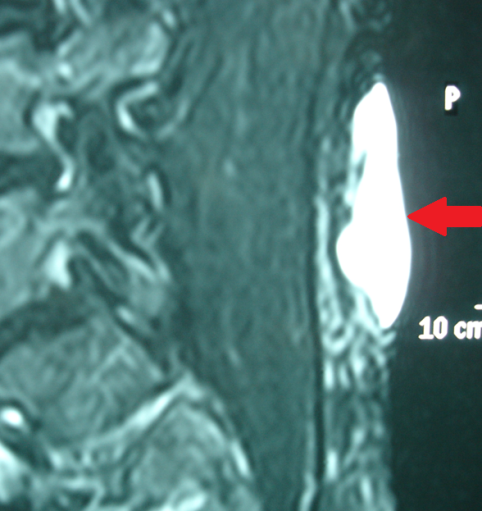

MRI οσφύος — Η βλάβη εμφανώς περιορίζεται στο δέρμα και τον υποδόριο ιστό (Ευγενική παραχώρηση Dr. V. Penopoulos)